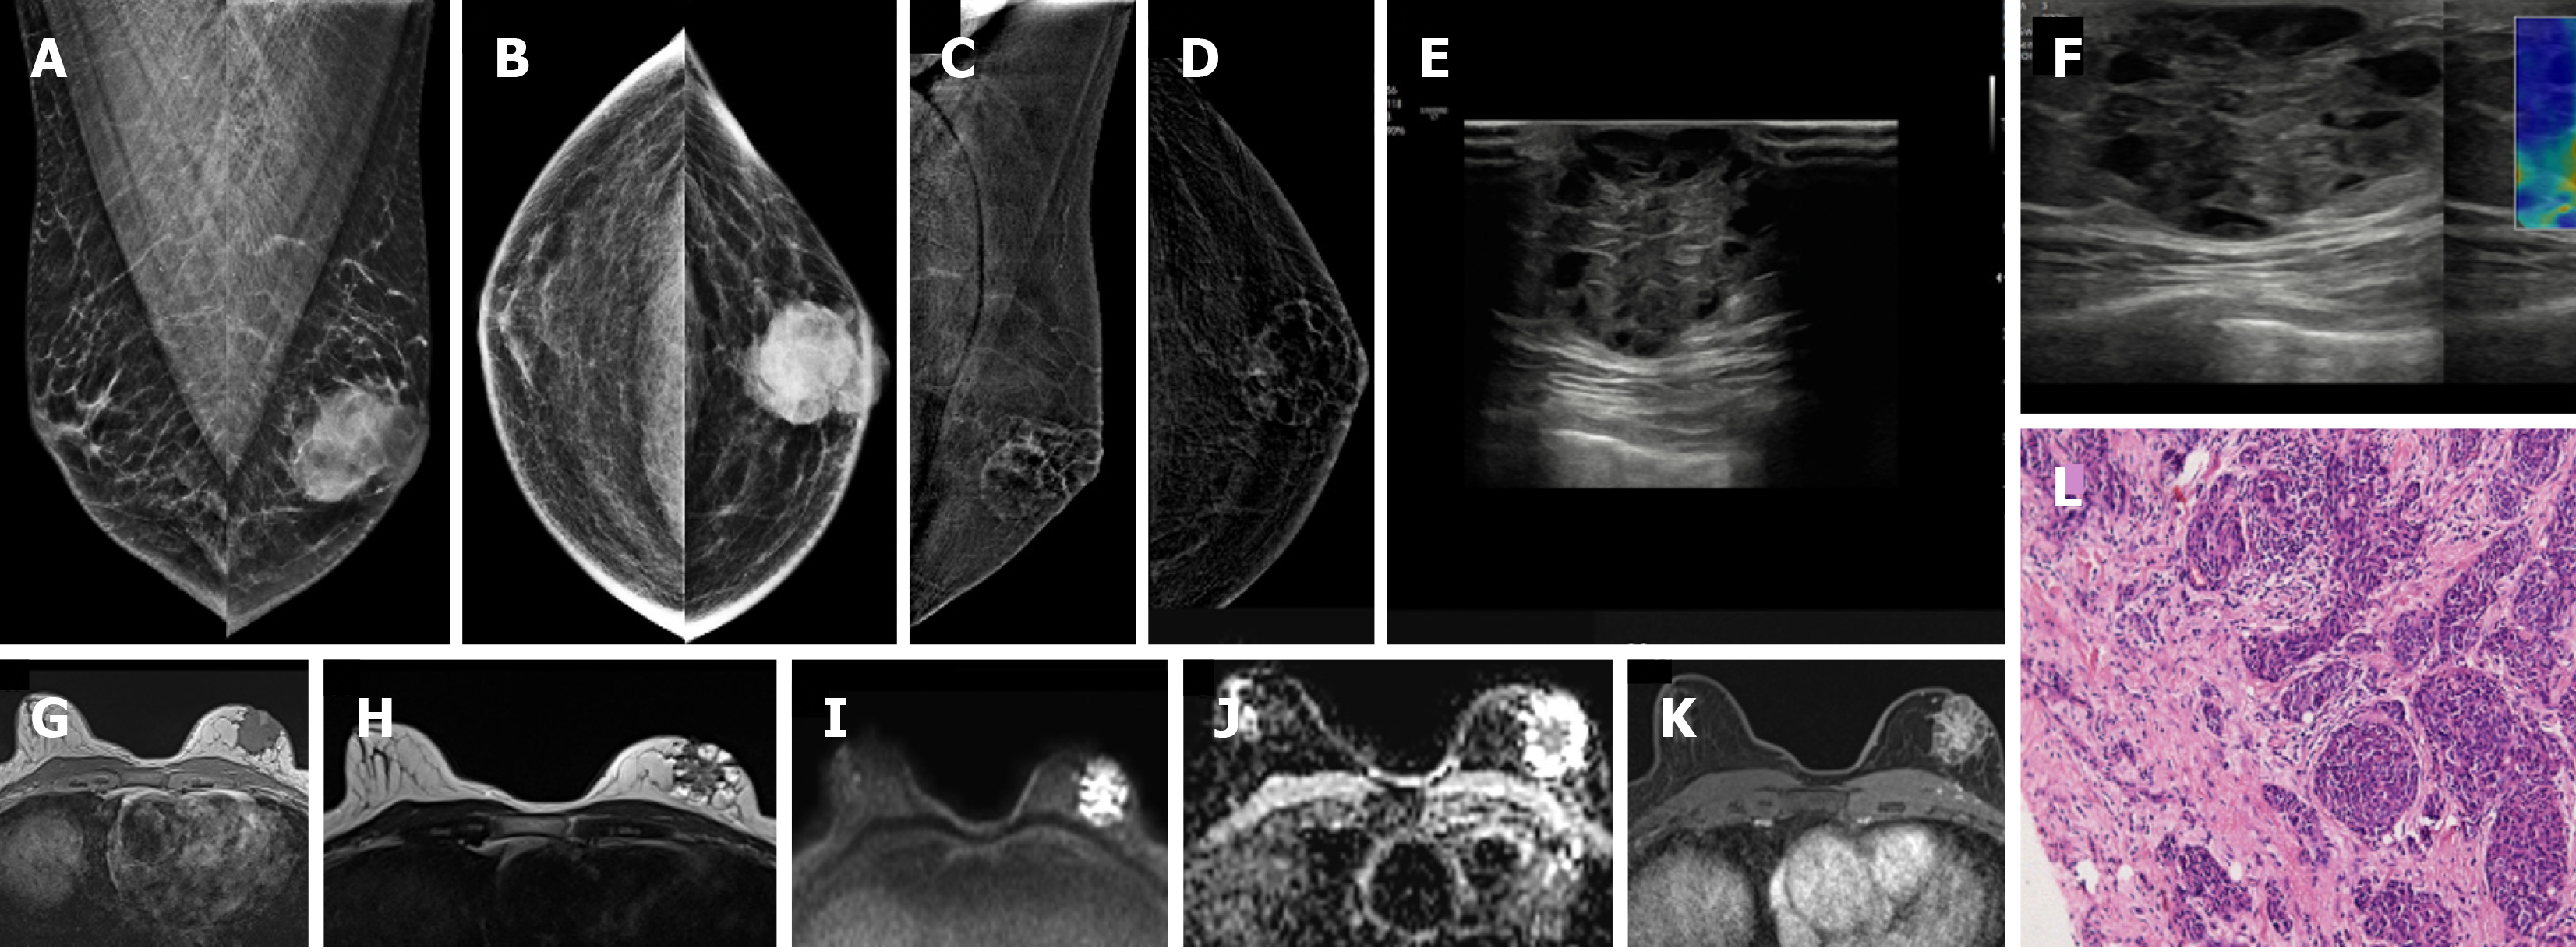

Figure 19  Invasive breast cancer in a 74-year-old male with a hard lump in left breast.

A: Mediolateral oblique (MLO) view; B: Craniocaudal (CC) view showing an irregular, high-density mass; C and D: Contrast-enhanced mammography; C: MLO and D: CC views of the recombined images showing heterogeneous enhancement; E: Ultrasound; F: Elastography images showing an irregular heteroechoic mass with microlobulated margins that appear hard on elastography; G-J: Magnetic resonance images showing an irregular mass; G: T1-weighted image showing a hypointense signal; H: T2-weighted image showing a heterogeneously hyperintense signal; I and J: DWI-ADC images showing central diffusion restriction; K: Postcontrast image showing heterogeneous septal enhancement; L: Histopathological examination image (hematoxylin–eosin, × 40) showing invasive breast cancer (no special type) composed of tumor cells arranged in clusters and tubules.

Figure 20  Invasive lobular carcinoma in a 65-year-old male with a hard retroareolar lump.

A: Mediolateral oblique; B: Craniocaudal mammography views showing an irregular high-density mass with spiculated margins, few punctate calcific foci and surrounding architectural distortion. Nipple retraction and overlying skin thickening are also observed; C: Ultrasound; D: Elastography images show an irregular mass with angular margins, which appears hard on elastography; E: Histopathology (hematoxylin and eosin, × 40); F: E-cadherin images show medium to small dyscohesive cells that lack E-cadherin expression.